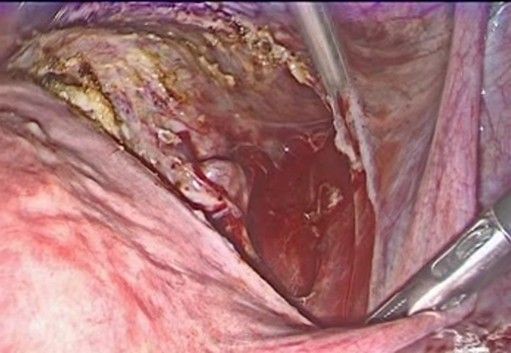

- Mersilene Ribbon Pass (Figure 7-10): A 5 mm Mersilene tape (or similar) is used, mounted on a semicircular needle or introduced using a laparoscopic forceps, the needle is introduced from the anterior aspect of the isthmus-cervix to the posterior aspect, medial to the uterine artery and just superior and medial to the uterine insertion of the uterosacral ligament close to the level of the internal cervical os. Care is taken to avoid injuring uterine vessels or penetrating the cervical cavity. The procedure is repeated symmetrically on the contralateral side, passing the tape from posterior to anterior, always medial to the uterine artery.

Figure 8: introduction of the needle in the anterior aspect of the cervix

Figure 9: the needle passes from the anterior aspect of the isthmus-cervix to the posterior aspect, medial to the uterine artery and just superior and medial to the uterine insertion of the uterosacral ligament close to the level of the internal cervical os